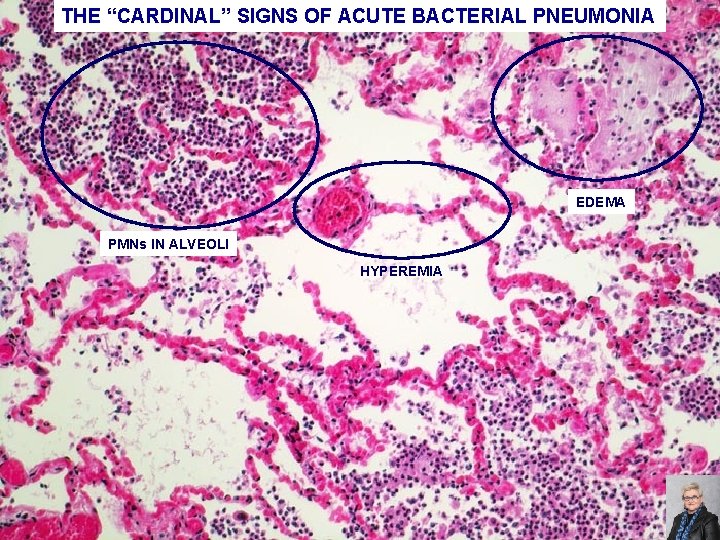

ACUTE BACTERIAL PNEUMONIA -PATCHY CONSOLIDATION -CARDINAL SIGNS OF ACUTE INFLAMMATION ARE PRESENT: HYPEREMIA EDEMA PMNs IN THE ALVEOLI 70

THE “CARDINAL” SIGNS OF ACUTE BACTERIAL PNEUMONIA EDEMA PMNs IN ALVEOLI HYPEREMIA 71